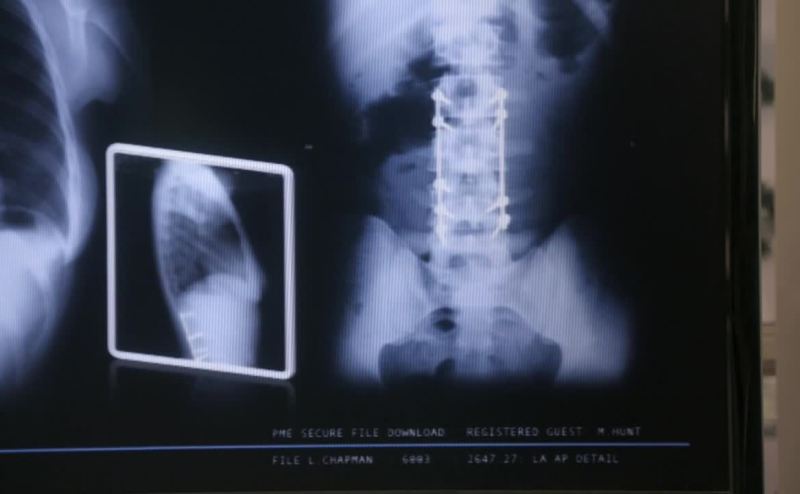

The scar down Linda's spine was

from a childhood accident.

She was hit by a car, broke her neck in three places.

That would explain the rods.